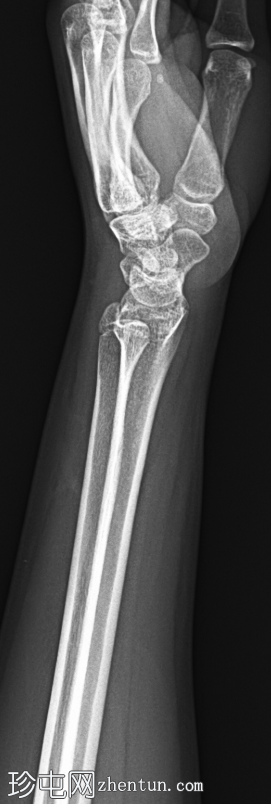

X线片

1.png

正位片

左腕正位X线片显示桡骨远端干骺端背外侧皮质轻微弯曲,无皮质破裂或移位。无明显成角畸形或尺骨骨折。关节间隙和腕骨排列正常。

最终诊断:桡骨远端干骺端轻微嵌插(弯曲型)骨折。